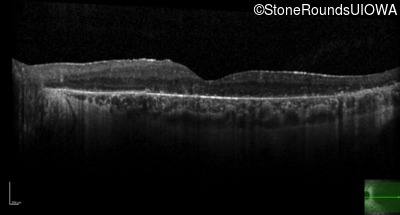

Optical Coherence Tomography - Right - 20/25 -1

Exemplar / OCT Stack

OCT Stack